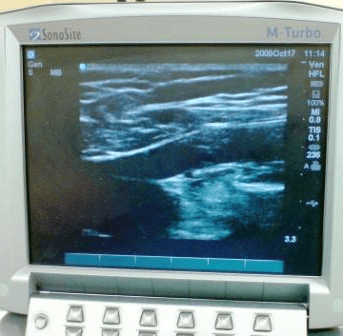

At your initial 30 min consultation the vascular surgeon who will perform a vein scan (doppler scan) to assess you further and decide the best way to treat your veins. This will involve putting some gel on your leg which can easily be washed off later. The surgeon will expose your whole leg from groin downwards to check your leg veins thoroughly. If you require a chaperone please let the doctor know.

Diagnosing which veins are faulty guides the vascular surgeon on how to treat the vein so this step is very important and is key to success of subsequent treatment. This scan is painless and is similar to scan in pregnancy. It does not involve X-rays.